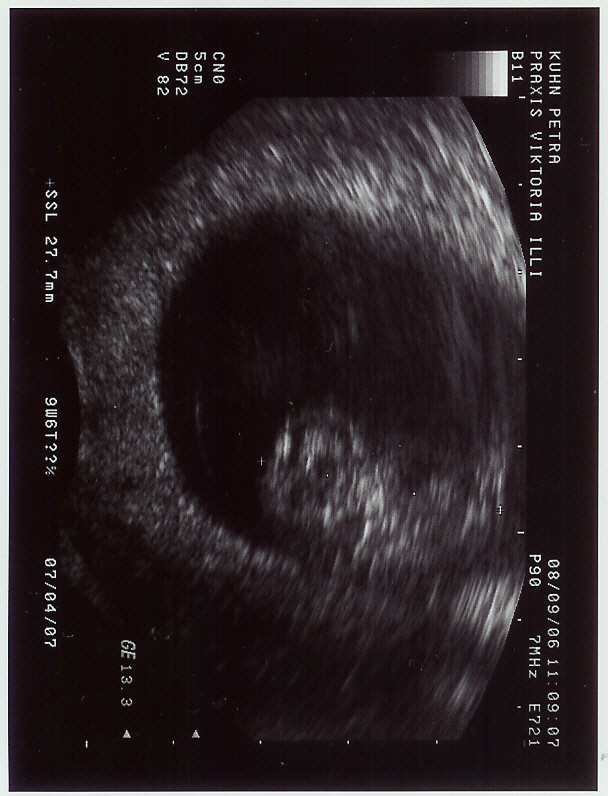

Mein Termin ist heute gut gelaufen. :D

Dem Krümel geht es gut und er ist kräftig gewachsen. :dance:

Jetzt schon 27,7 mm groß. :o

Vor zwei Wochen war er noch zwei Tage hinter dem ET

und jetzt ist er dem ET schon vier Tage voraus. :dance: :dance:

Mausi: Schön,dass mit Krümelchen alles in Ordung ist und man kann ja schon gut was erkennen! :knuddel: :knuddel: :knuddel: Guuut gemacht!! :knuddel: